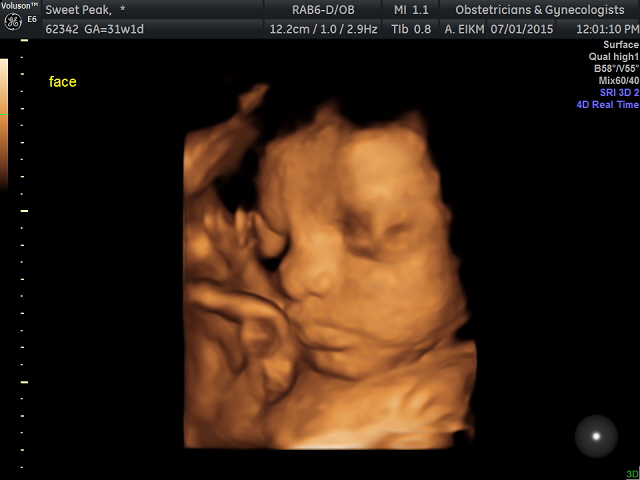

Here are some of mine. I didn't get a good view of his face during the anatomy scan, so I decided to do the elective. My little boy is 31 weeks :)